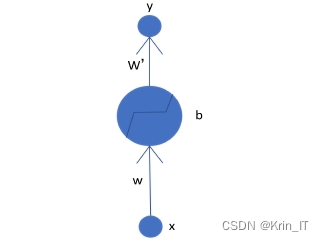

深度卷积神经网络(DCNN)是通过多次叠加普通卷积神经网络构建而成的,网络的层数越多,模型的深度越大。DCNN的设计灵感来源于生物神经系统,其中神经元模型是人工神经网络的基本构成单元,它将生物神经细胞的信号传递及激活过程抽象为数学模型。这种深度结构使得DCNN能够有效提取数据中的层次特征,特别适用于复杂的图像识别和处理任务。